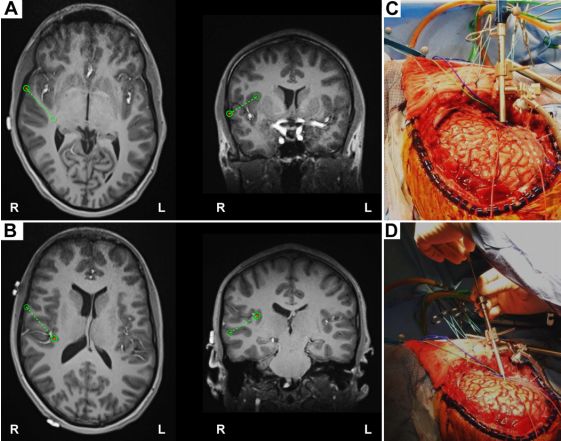

21.基于颅内电极研究:颞极在颞叶癫痫发作网络中的作用

Role of the temporal pole in temporal lobe epilepsy seizure networks: an intracranial electrode investigation.

PMID: 29027858 DOI: 10.3171/2017.3.JNS162821

颞叶(temporal pole, TP)在颞叶癫痫(temporal lobe epilepsy, TLE)发作和传播过程中有着重要作用。研究对10例患者行慢性皮层脑电图(electrocorticography, ECoG)监测,特制的密集电极覆盖颞极,以确认痫灶位置。所有患者最终行皮层-杏仁核-海马切除术,并对所有患者的临床记录结果进行回顾,包括ECoG结果、神经影像、神经病理学和临床预后。

结果显示,70%的患者有颞极痫性发作和发作间期放电,颞极在颞叶癫痫发作网络中有重要作用。而依据影像和记录到的发作间期放电并未包含颞极。因此,研究者建议,在对行TLE手术前应考虑颞极的致痫因素,特别是考虑选择性颞内侧切除手术时。

【李信晓】